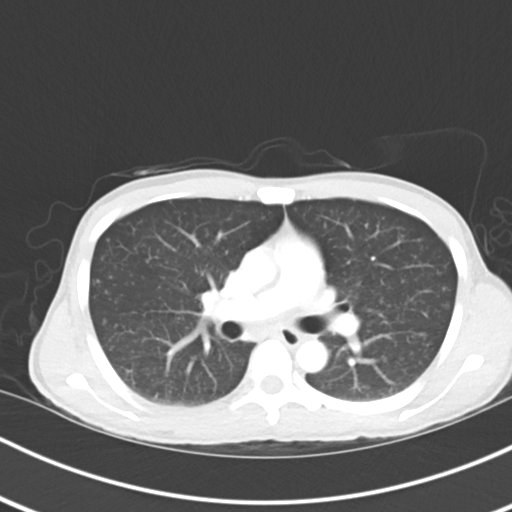

Miliary TB, CT, Unannotated. JETem 2020

A Case Report on Miliary Tuberculosis in Acute Immune Reconstitution Inflammatory Syndrome